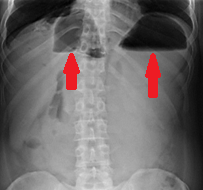

Αμφοτερόπλευρη αυτόματη νεφρική αιμορραγία — κοκκιωμάτωση Wegener (Ευγενική παραχώρηση Dr. V. Penopoulos)